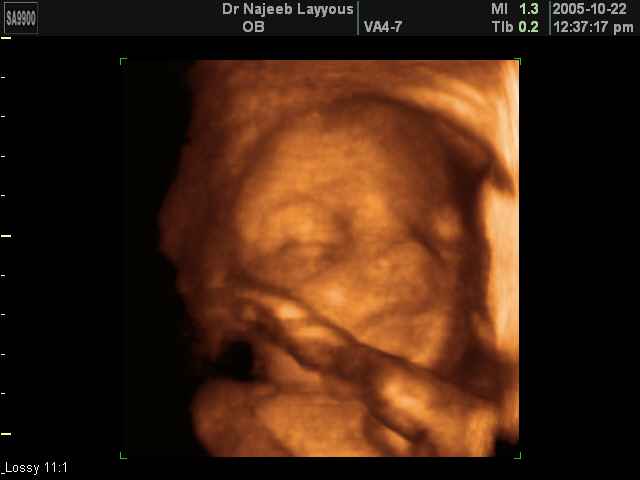

صور لتصرفات الجنين داخل الرحم بجهاز الالتراساوند ثلاثي الأبعاد | الدكتور نجيب ليوس

صور بجهاز الموجات فوق صوتية ثلاثي الأبعاد لتصرفات الجنين داخل الرحم